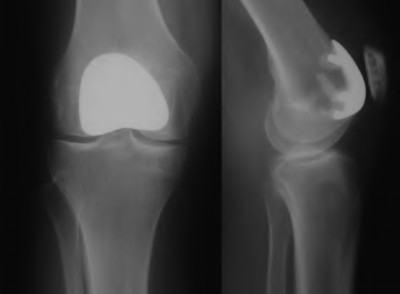

A 60-year-old male tennis player undergoes a unicompartmental knee arthroplasty (UKA) shown in Figures A and B. Which of the following statements regarding this procedure is true?

1) Compared to total knee arthroplasty (TKA), UKA more closely approximates native knee kinematics

Figures A and B depict radiographs of a unicompartmental knee arthroplasty (UKA). UKA kinematics have been shown to most closely approximate native knee kinematics.

In an in vitro cadaver study, Patil et al found that TKA significantly changed knee kinematics while the unicompartmental replacement preserved normal knee kinematics.

Fisher et al performed a retrospective study comparing the short-term outcomes of small-incision unicompartmental knee arthroplasty (UKA) with standard total knee arthroplasty (TKA) in 91 consecutive patients older than 70 years. They found: 1) Blood loss was significantly more for the TKA group, as was the need for blood transfusion. 2) Patients with unicompartmental replacements had a much quicker return of function and discontinuation of pain medication. 3) While knee scores and ROM were similar preoperatively, both were better in the unicompartmental group at each postoperative time interval. 4) Narcotic use and length of hospital stay were also significantly less for the unicompartmental group. Therefore answers 2,3,4 and 5 are false.